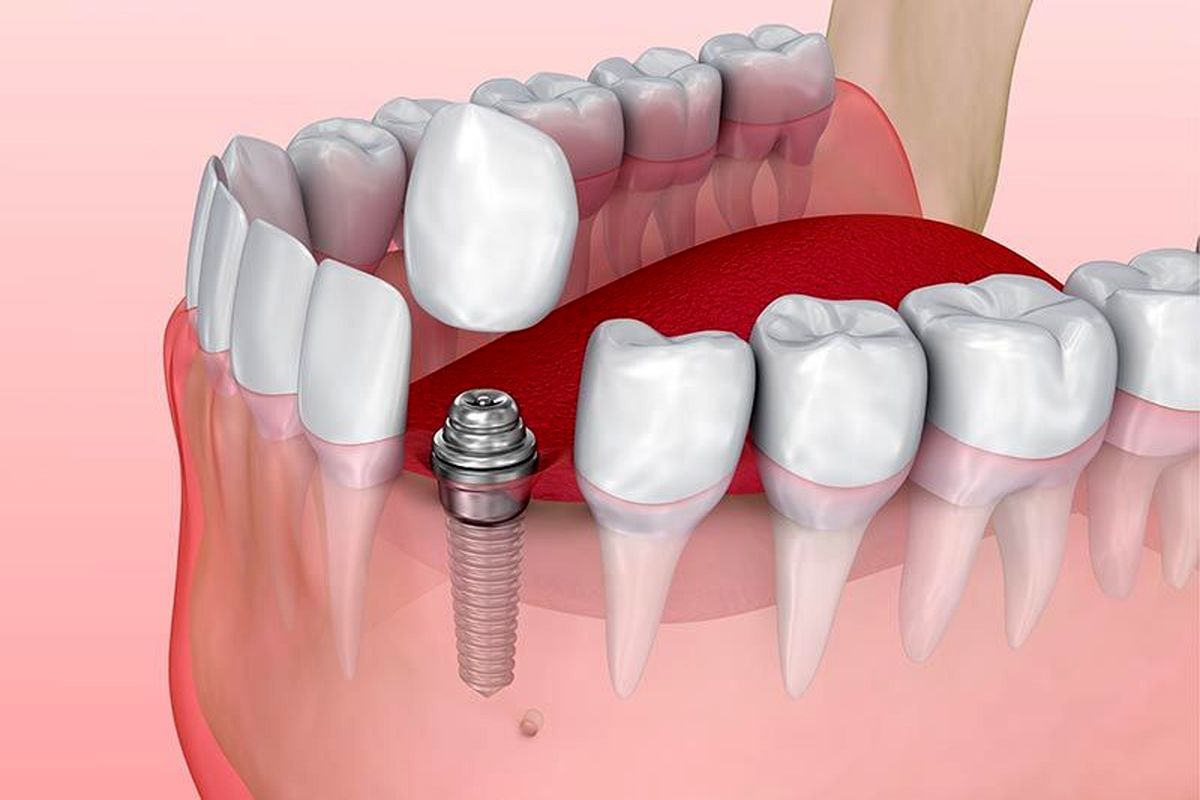

ایمپلنت دندان نوع دیگری از دندان مصنوعی است که بسیار کاربردی تر و بهترین جایگزین برای دندانهای از دست رفته شما می باشد این نوع دندان مصنوعی را می توان جزو پروتزهای ثابت دندانی قرار داد زیرا پس از قرار گرفتن در جای خود دیگر امکان جابجایی وجود ندارد و همانند دندانهای خود می توانید از آن به راحتی و بدون مشکل و درد استفاده کنید.

اجزای تشکیل دهنده ایمپلنت دو جزء اند که هر کدام از آنها در مرحله خاصی توسط متخصصین دندانپزشک در دندان از دست رفته شما قرار می گیرند این دو جزء عبارتند از:

فیکسچر ایمپلنت یا پایه ایمپلنت

فیکسچر ایمپلنت یا همان پیچ ایمپلنت است که جزء اصلی ترین اجزاء ایمپلنت به شمار می آید و در مرحله اول کاشت دندان در لثه توسط پزشک قرار می گیرد که جنس این پیچ از تیتانیوم سازگار با بافت بدن است و در مدت کوتاهی با لثه فرد جوش خورده و ثابت می شود.

روکش و پروتز دندانی

جزئی است که بر روی پایه ایمپلنت قرار گرفته و سالهای سال بر روی پیچ زیرین واقع می شود و هیچ گونه آسیبی به پایه ایمپلنت وارد نمی کند. روکش پروتز همیشه بعد از جوش خوردن کامل پیج ایمپلنت بر روی لثه قرار می گیرد و زیبایی دندان شما در هنگامی که روکش قرار میگیرد ظاهر می شود و متوجه خواهید شد که هیچ تفاوتی با دندانهای واقعی خود احساس نخواهید کرد.